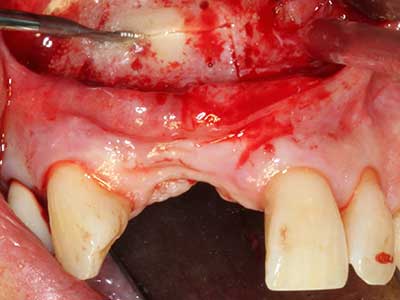

Bei der Knochenblockentnahme zeigen sich weitere Vorteile für die Piezochirurgie: Neben der bereits beschriebenen hohen Präzision bei der Osteotomie stellt sich gerade die Verwendung der dünnen Sägespitzen als besonders materialschonend heraus. Bei der Verwendung insbesondere von Lindemannfräsen sind mit deutlich höheren Entnahmeverlusten durch die dickere Instrumentenspitze zu rechnen (Lakshmiganthan, Gokulanathan et al. 2012). Die insbesondere bei retromolar entnommenen Blocktransplantaten notwendige basale Abtrennung wird durch speziell hierfür vorgesehene rechtwinklige Sägen erleichtert, so dass die Piezochirurgie als präzises, übersichtliches und sicheres Verfahren zur retromolaren Knochenblockgewinnung angesehen wird (Happe 2007) (Abb. 1-12).

Indikation: Bone Splitting